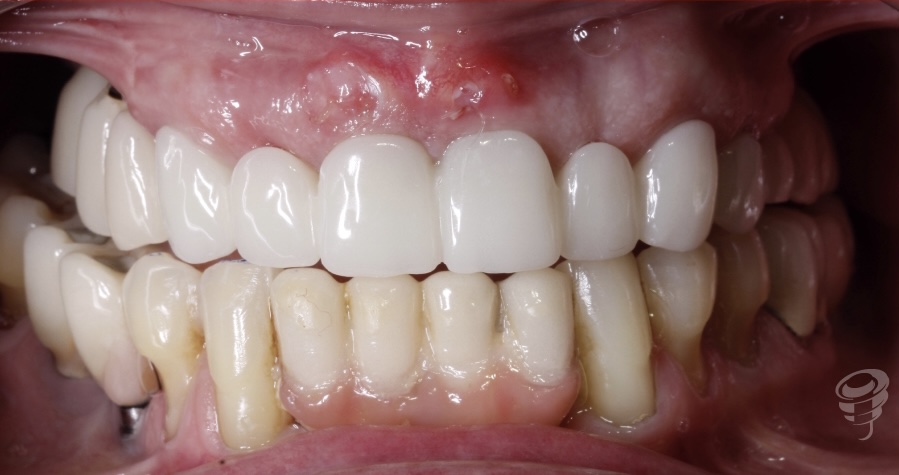

Situación prospto perio después de 2 meses con los perfiles de emergencia personalizados

Figura 14

Figura 15

Desgastamos la zona estética de la prótesis (11-21) para crear espacio y así conseguir la recolocación del margen gingival.

3er Prótesis Provisional, impresa con resina Bego TRINI-Q, luego de conformación personalizada analógica de los perfiles de emergencia.